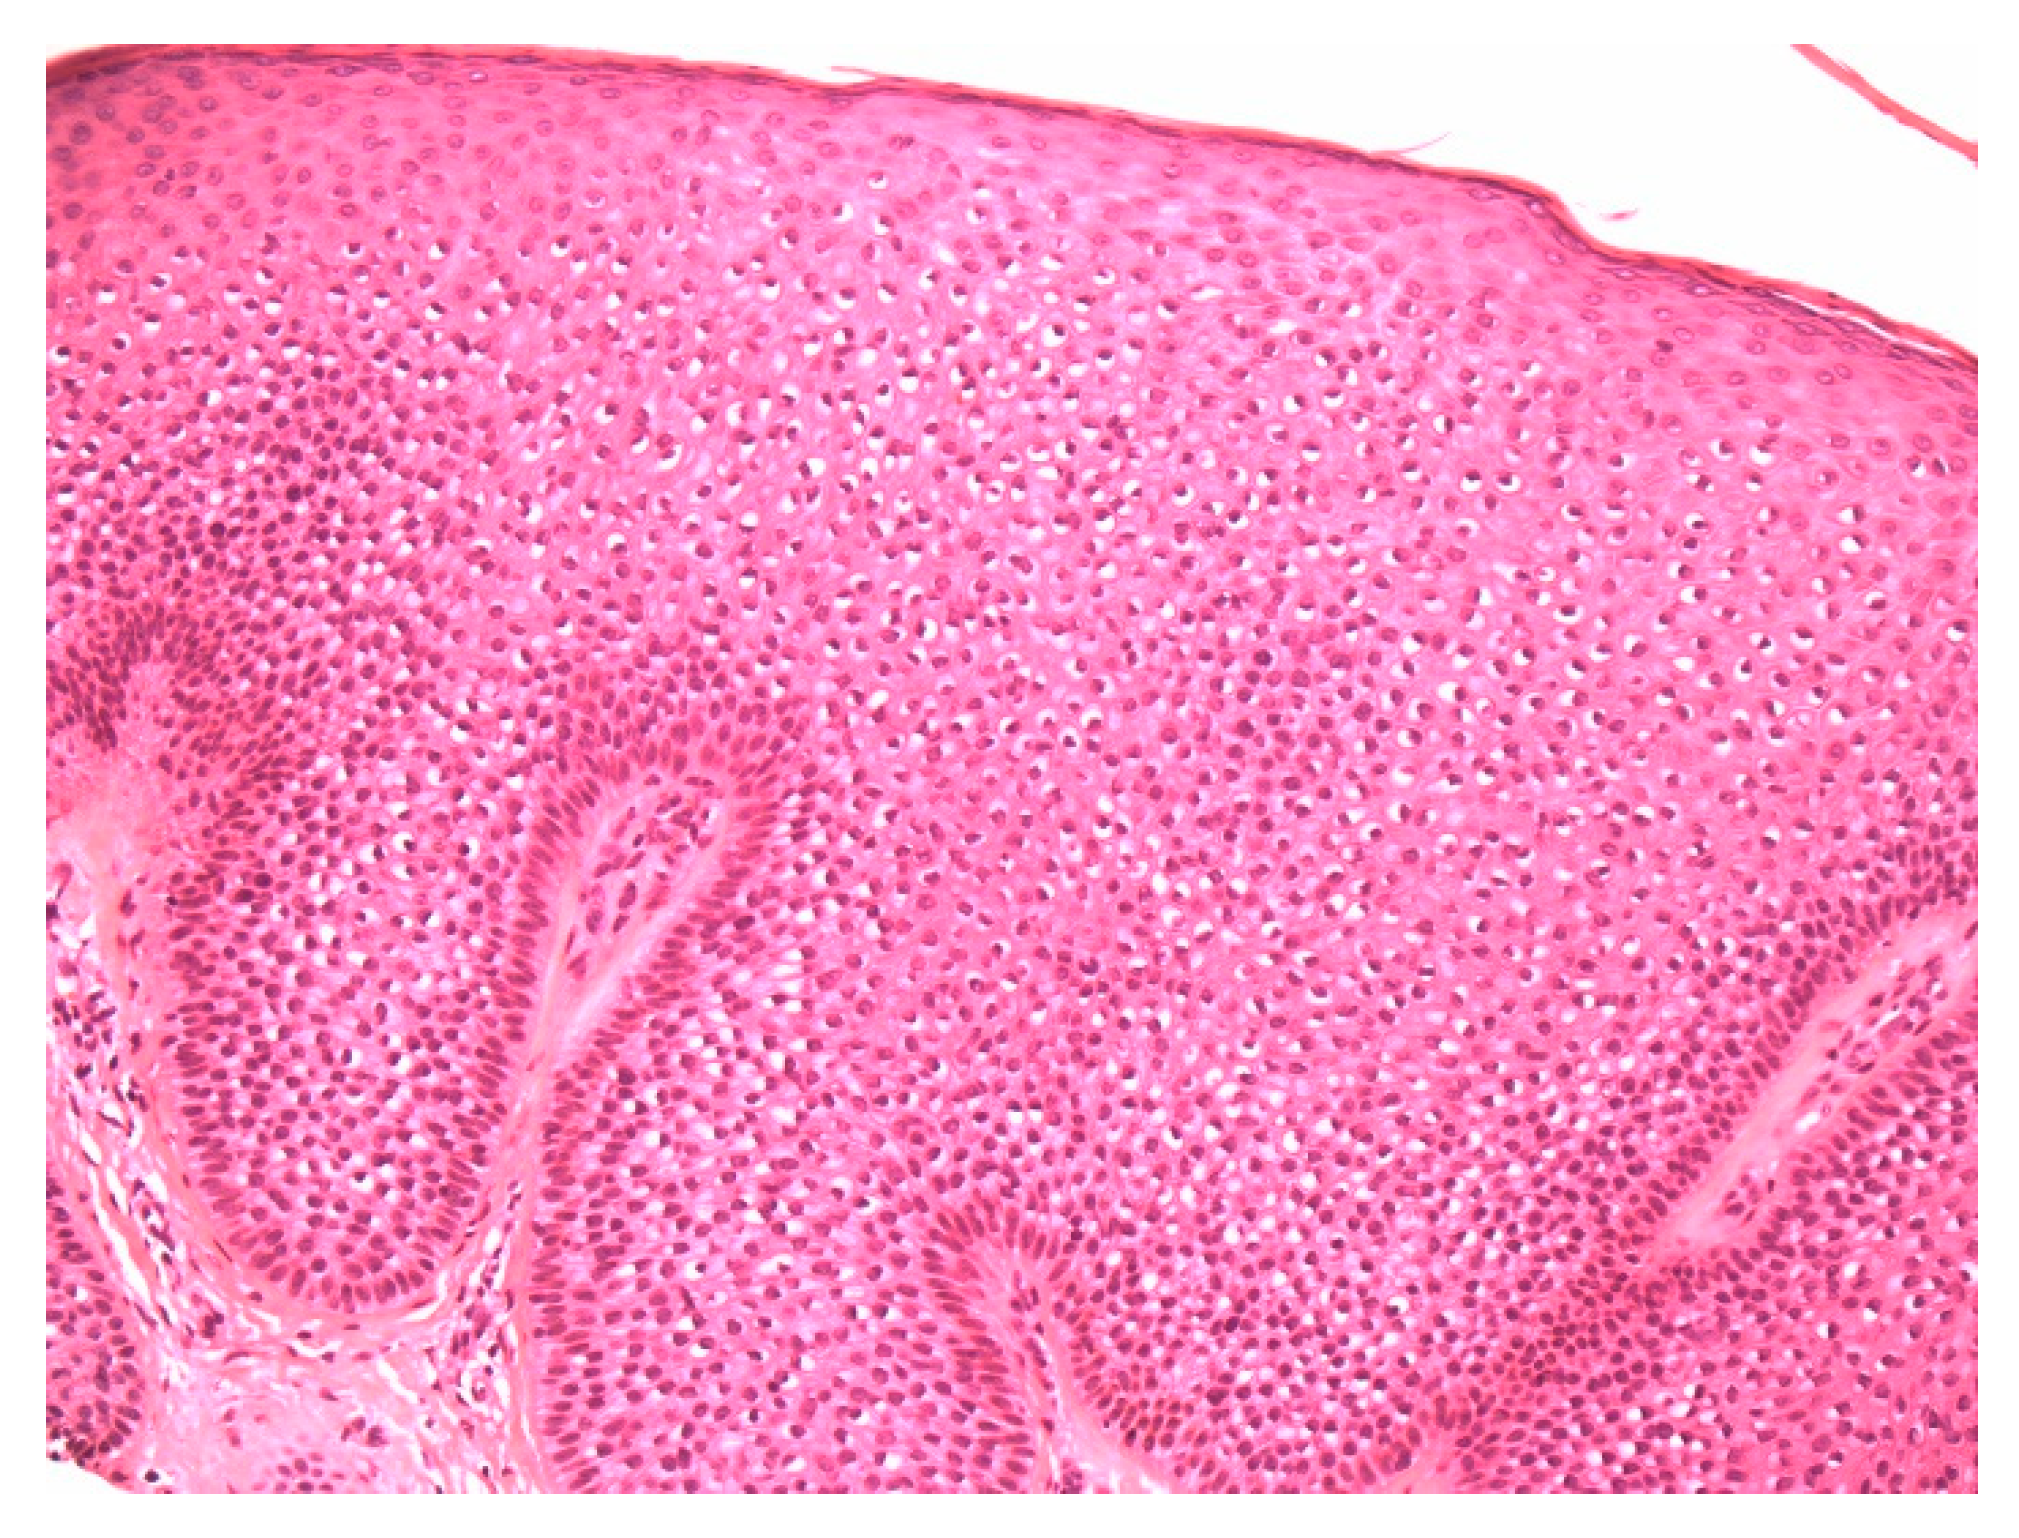

Figure 1.

A dome-shaped lesion exhibits pale keratinocytes with a large perinuclear vacuole reminiscent of trichilemmal differentiation.